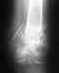

Вот выписка и результаты узи

Нога постоянно похрустывает. При ходьбе нога побаливает и отекает, раньше такого не было. Не думаю, что это связанно с наследственным заболеванием, так как после операции был наложен коксид и 4 месячная иммобилизация голеностопного, коленного и тазобедренного сустава , а с этими суставами все относительно нормально. Мое наследственное заболевание не то, которое поражает один коленный сустав.

1.Как думаете: У меня есть артроз или анкилоз? Полная разработка возможна ?

2. Это врачебная ошибка? Написали, что это набмыщелковая остеотомия, фиксация спицами, а сделали межмыщелкову.